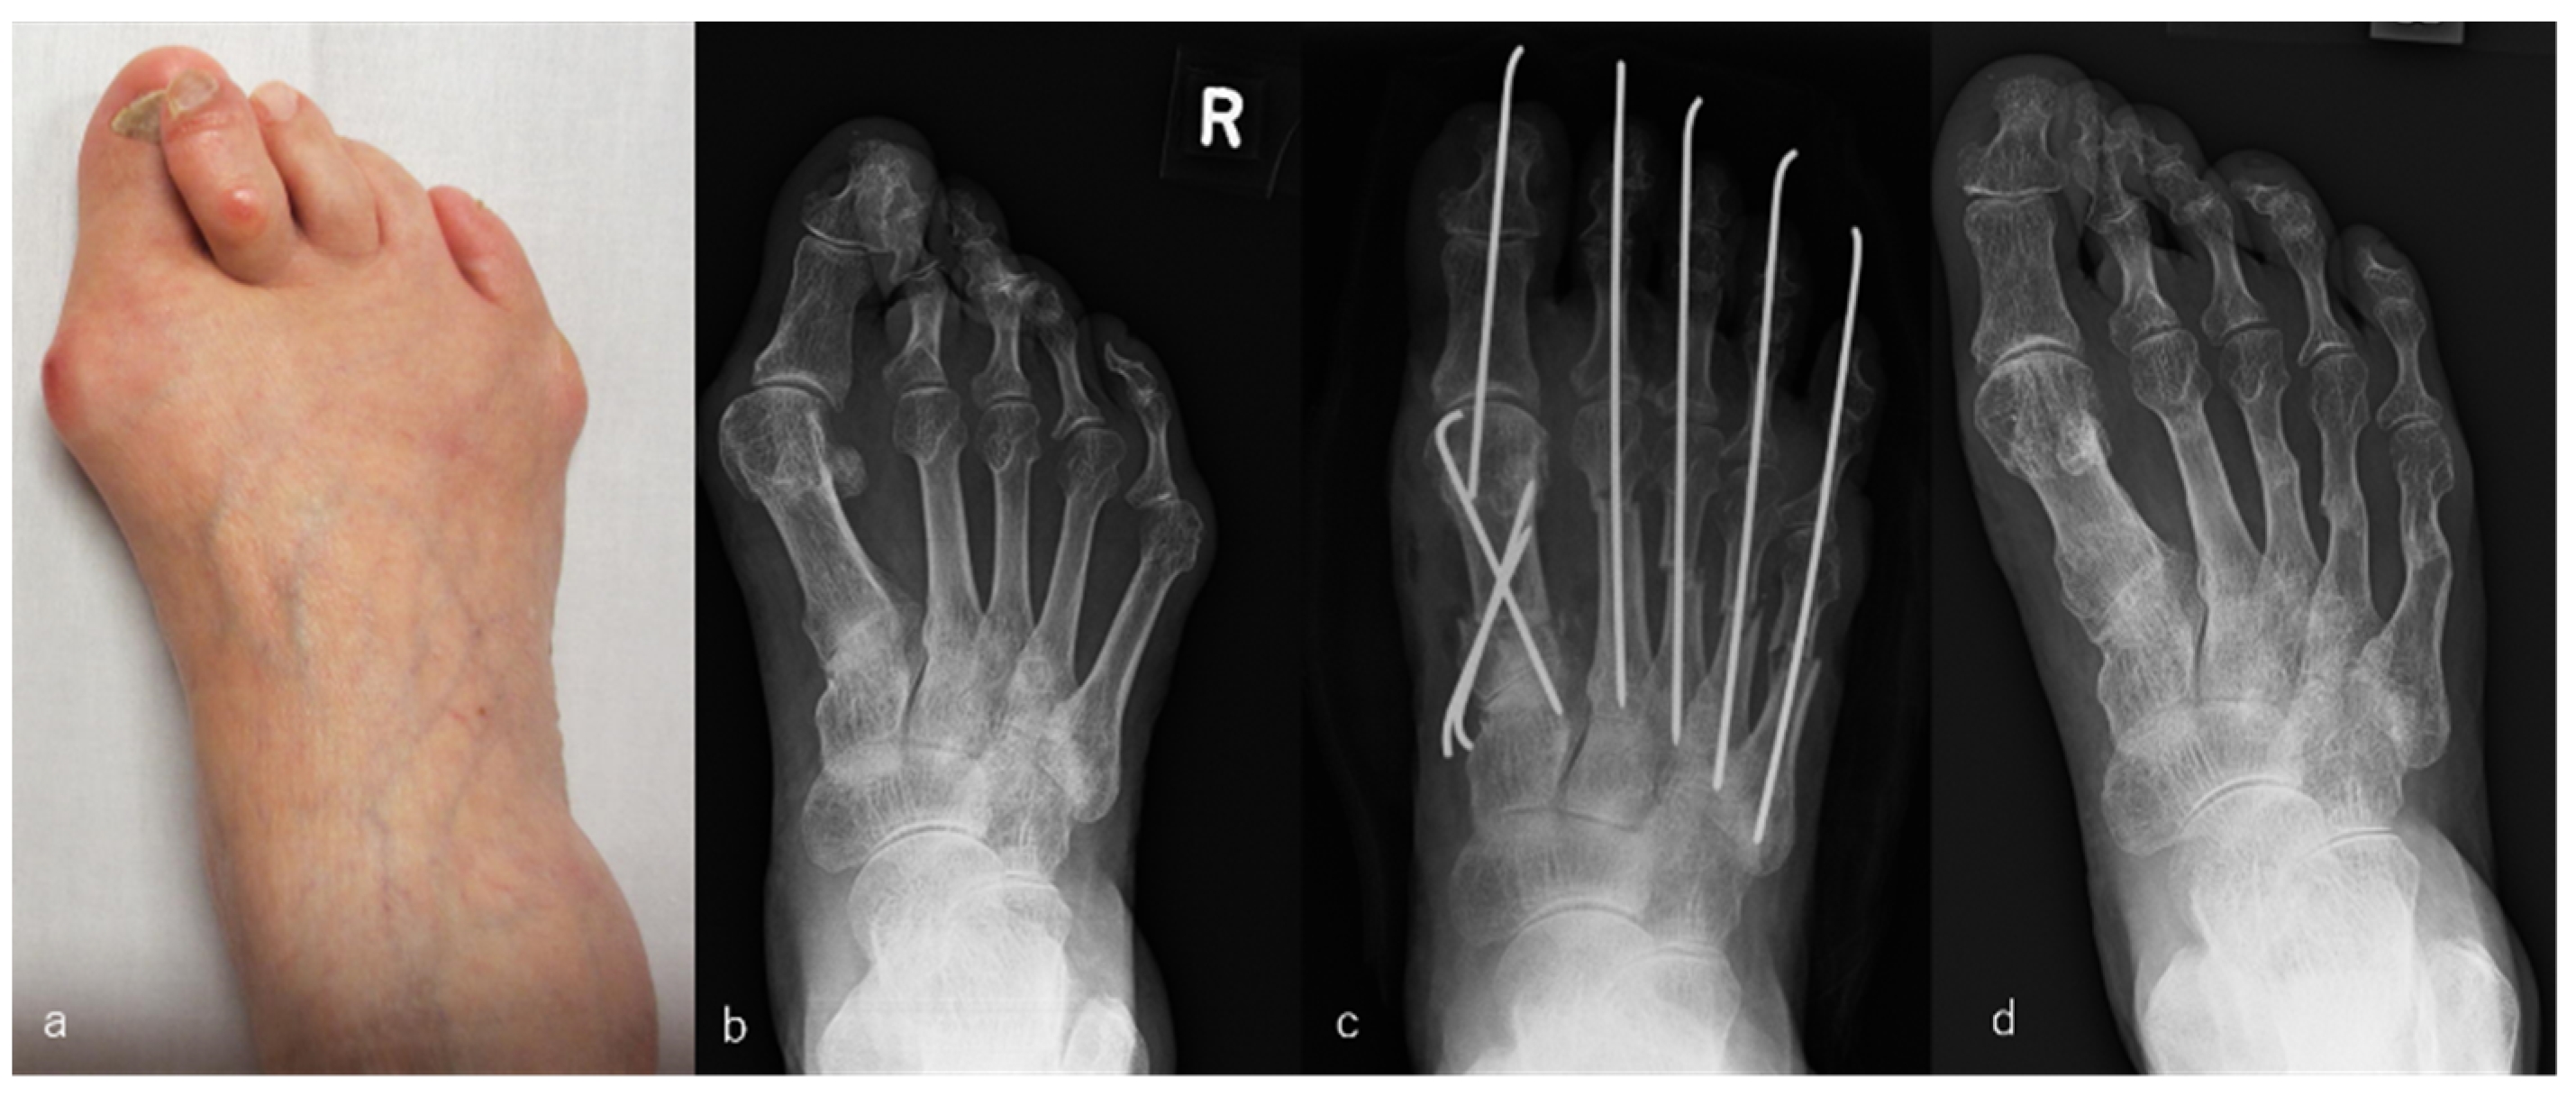

For the PP group, the modified Mann method was used in combination with (a) elevation of the abductor hallucis tendon, which was dislocated to the plantar side of the big toe toward the tibial side of the metatarsal bone; (b) cutting of the MTP joint capsule of the big toe on the tibial side in a Y-shape, which was plicated and shortened for the closing of the joint capsule after the modified Mann osteotomy; (c) partial resection of the distal end of the adductor hallucis tendon and transverse metatarsal ligament from the lateral aspect of the fibular sesamoid and base of the proximal phalanx; (d) removal of the connective tissue that was inflamed as a result of bunions; (e) proximal osteotomy of the metatarsal bone for the shortening and correction of the varus deformity and its internal rotational deformity with the use of a fixed 1.6-mm Kirschner wire; and (f) offset osteotomy of the metatarsal bone with the MTP joints of the lesser toes [6]. An example is shown in Figure 1.

Figure 1.

Rheumatoid arthritis (RA) in a 78-year-old woman. Metatarsophalangeal joint-preserving surgery was performed involving the modified Mann method for the big toe and offset osteotomy for lesser toes. RA had been present for 6 years. The patient received bucillamine (200 mg/day) and sulfasalazine (1000 mg/day). Macrographic and radiographic views of her right foot before surgery (a,b), immediately after surgery (c), and 7 years after surgery, which was the latest follow-up (d). The score on the Japanese Society for Surgery of the Foot RA foot and ankle scale improved from 40 points before surgery to 92 points at the 7-year follow-up. The mean hallux valgus angle improved from 45° before surgery to 14° immediately after surgery and was 19° at the 7-year follow-up. The patient was satisfied with the clinical results at the 7-year follow-up, although the correction of the hallux valgus angle had decreased slightly compared with that immediately after surgery.